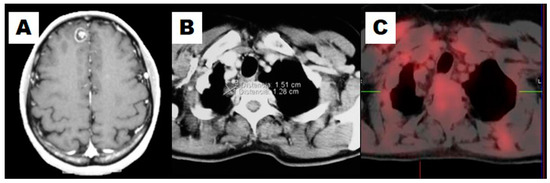

Figure 2.

This example illustrates how 18F-FDG PET/CT would rule out the suspicion of recurrence. A resectable isolated cerebral lesion was diagnosed in a 48-year-old female after treatment of NSCLC (A); She had a previous lobectomy and a left adrenalectomy. Taking into account the resectability of the cerebral lesion, a CT for restaging showed a solitary nodule in the right upper lung (B); An 18F-FDG PET/CT showed no pathological uptake in the lung nodule (C). The patient was treated with stereotaxic surgery over the cerebral lesion. Three years later, she remained asymptomatic.